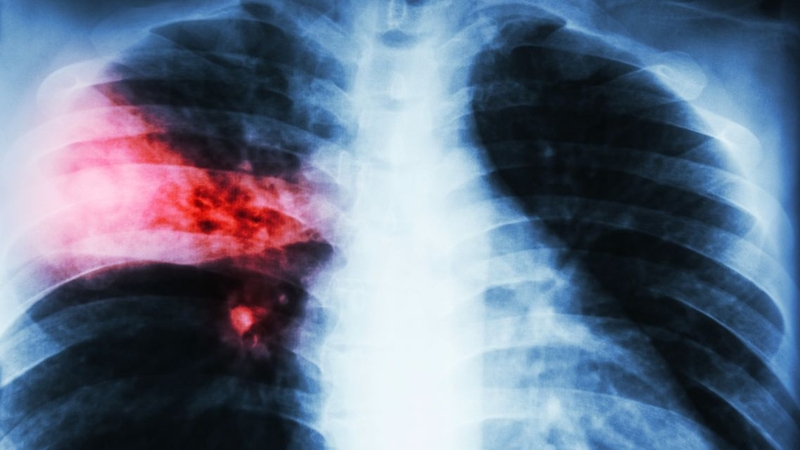

Khi bị viêm phổi kèm theo ho ra máu, người bệnh thường có thêm các dấu hiệu như sốt, đau tức ngực, khó thở và ho có đờm lẫn máu. Kết quả chụp X-quang phổi sẽ cho thấy vùng phổi bị viêm. Máu ho ra thường có màu đỏ tươi hoặc đỏ sẫm, lượng máu có thể ít hoặc nhiều tùy mức độ tổn thương phổi.

Để xác định chính xác nguyên nhân ho ra máu, phân biệt viêm phổi ho ra máu với các bệnh lý khác, bác sĩ cần kết hợp đánh giá triệu chứng toàn thân, khai thác tiền sử, xét nghiệm cận lâm sàng như X-quang, CT scan, xét nghiệm máu. Nếu cần thiết, bác sĩ sẽ chỉ định sinh thiết hoặc nội soi phế quản.